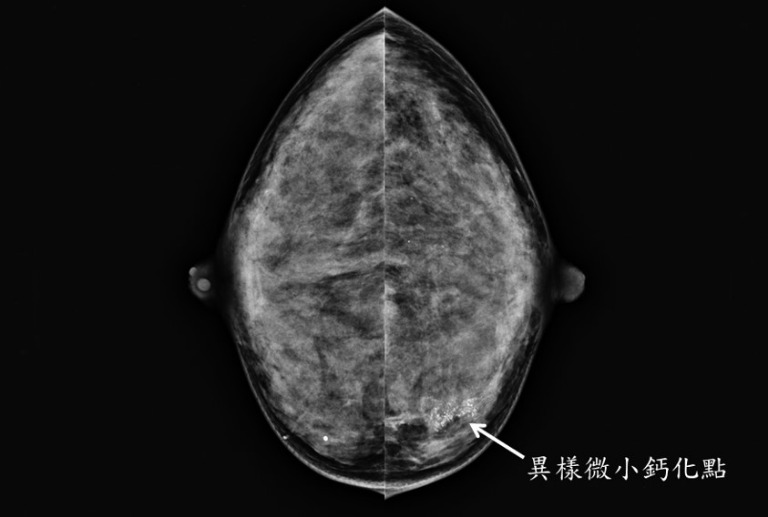

早期乳癌大部分妳都不會有任何症狀或不舒服,尤其零期乳癌(即原位癌) 臨床上常常無任何症狀,但卻以異樣微小鈣化點為表現,在施行乳癌篩檢接受乳房X光攝影時意外早期發現(圖1);等妳發現乳房或腋下有明顯硬塊或腫瘤、乳房變形、乳房皮膚有潰瘍或橘皮狀變化時大多已不是早期乳癌。甚至臨床症狀因骨頭轉移呈現骨頭疼、肺部轉移呈現呼吸困難、肝臟轉移呈現肝機能衰竭、腦部轉移呈現頭痛,神智昏迷時已經是四期乳癌而無法根治痊癒(圖2)。